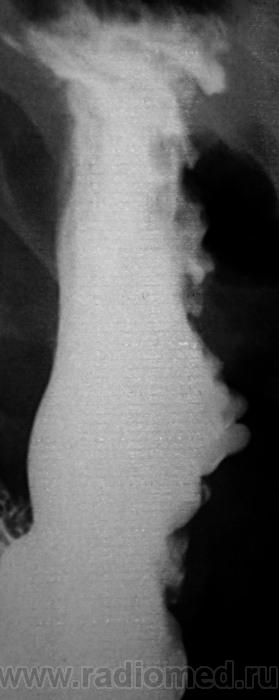

Варикозные вены?

Большая кривизна у тела желудка странная.

Да, для нормы странноватая.

Лежа бы вниз головой... Ну а так, дефект наполнения по большой кривизне свода. М.б. что угодно, больше за гиперплазию или онко.

Почему не локальная форма Менетрие?....

"Картинка" то типичная, именно, для болезни Менетрие.

Снимок не один, выставлен один для "мозгового штурма".

Пациент наблюдается уже в течение пяти лет, консультирован, обследовался и лечился в ОКБ.